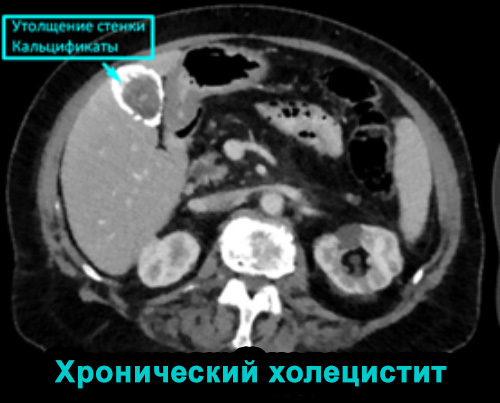

Хронический холецистит развивается после острого холецистита. Хроническое течение холецистита является одной из причин развития злокачественных патологий.

Компьютерную томографию при диагностике хронического холецистита назначают с целью обнаружения возможных осложнений, а также при проведении дифференциальной диагностики.

ХРОНИЧЕСКИЙ ХОЛЕЦИСТИТ

Хронический холецистит может быть причиной развития рака желчного пузыря